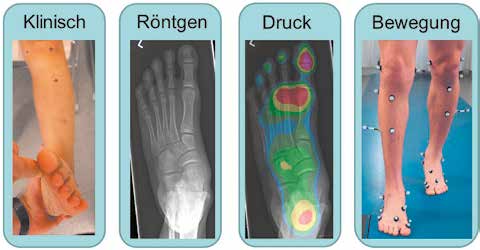

Während des Gehens hat der Fuß die Aufgabe, beim initialen Bodenkontakt den Aufprall zu dämpfen und sich danach in der Standphase an Unebenheiten des Bodens anzupassen, um eine sichere Auflagefläche zu gewährleisten. Beim nachfolgenden Abdruck sollte der Fuß einen steifen Hebel bilden, um die Kraft der Wadenmuskulatur effektiv zum Vortrieb zu nutzen 1. Sind diese Funktionen gestört, klagt der Patient häufig über Symptome wie rasche Ermüdung des Fußes, Schmerzen und Einschränkungen bei der Sportausübung. Zur Diagnostik der Fußfunktion für eine zielgerichtete Planung der Therapie mit Einlagen, Orthesen oder operativen Eingriffen haben sich Fußmodelle etabliert 2. Fußmodelle sind biomechanische Computermodelle zur Berechnung von Gelenkbewegungen im Fuß, basierend auf Kameraaufnahmen der Bewegung. Ein Fußmodell steht hierbei nicht alleine; es wird als sinnvolle Ergänzung der manuellen Tests von Beweglichkeit und Kraft, des Röntgenbildes und der dynamischen Druckverteilungsmessung angesehen, die in ihrer Zusammenschau bewertet werden (Abb. 1). Die Vorteile eines Fußmodells gegenüber den anderen drei Messmethoden liegen auf der Hand: Bei der Bewegung wirken oft höhere Kräfte, als der Untersucher im manuellen klinischen Test aufbringen kann. Im Gegensatz zum statischen Röntgenbild bildet eine dynamische Messung die Fehlstellungen bei Bewegung und deren muskuläre Kompensationen besser ab. Gegenüber der zweidimensionalen Druckverteilungsmessung stellt sie eine dreidimensionale Messung der komplexen mehrdimensionalen Fußbewegung dar.

Das Fußmodell ist geeignet für die zielgerichtete Planung der Therapie von Fußdeformitäten mit Einlagen, Orthesen oder bei operativem Vorgehen als sinnvolle Ergänzung zur bisherigen Diagnostik (siehe Abb. 1). Die Messung sollte wegen der direkt auf die Haut aufgebrachten Marker möglichst barfuß erfolgen, sodass eine Messung des Effektes von Einlagen oder Orthesen im Schuh nur eingeschränkt möglich ist, indem man kleine Löcher in den Schuh schneidet und somit das Schuhwerk zerstört 20. Die Versorgung z. B. mit Funktioneller Elektrostimulation (FES) zur Behandlung der Fußheberschwäche bildet hierbei eine Ausnahme. FES benötigt keine mechanische Korrekturwirkung am Fuß, da sie direkt auf den Peronealnerv wirkt und ein Fußmodell in der Lage ist, Fußhebung und Korrekturwirkung der damit verbundenen Fußdeformität nachzuweisen und optimal einzustellen, wie im nachfolgenden Beispiel erläutert wird.